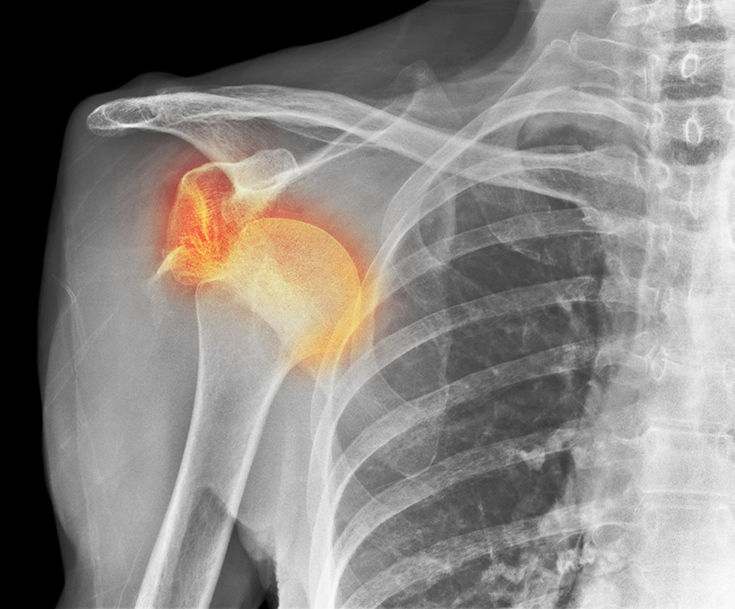

회전근개

회전근개는 어깨 관절을 둘러싸는 4개의 힘줄을 말하며, 이 힘줄들은 어깨 관절의 안정성을 유지시키고 어깨 관절을 움직이게 하는 역할을 합니다. 회전근개는 주로 퇴행성 변화와 반복된 사용으로 인해 힘줄이 약해지면서 손상이 발생하게 되고, 일부는 외부의 강한 충격 등 외상에 의해 파열되기도 합니다.

오십견

오십견은 동결견, 유착성관절낭염이라고도 불리며 어깨 관절 주위 연부조직의 염증성 변화로 인해 발생하며, 주로 50대에서 많이 발병한다고 하여 오십견이라고 불립니다. 이 질환의 특징은 어깨관절의 통증, 어깨 운동 장애, 능동적, 수동적 운동 범위의 감소라 할 수 있습니다.

충돌증후군

어깨를 움직일 때마다 어깨 관절을 처마처럼 덮고 있는 뼈(견봉)와 어깨 관절을 둘러싸고 있는 힘줄(회전근개)이 반복적으로 충돌하게 되면서 통증이 발생하는 질환이 어깨충돌증후군입니다. 뼈와 힘줄이 반복적으로 충돌하게 되면 사이의 점액낭에 염증이 발생하여 통증으로 나타나고, 점차 어깨 힘줄의 섬유화, 퇴행성 변화가 일어나게 되면서 심해지면 어깨 힘줄이 파열되기도 합니다.